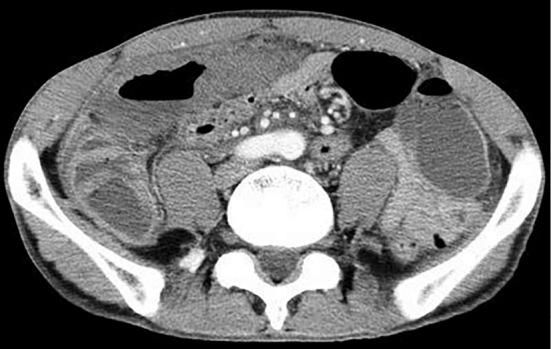

A 45-year-old man was admitted with acute abdominal pain and eosinophilia. Abdominal computed tomography revealed thickness of the ascending and transverse colon with decreased contrast enhancement and a small amount of ascites. In an emergency operation, the necrotic colon was resected. Histopathology showed subserous medium-sized arteritis with abundant eosinophil infiltrates and thrombosis in the portal vein branches. He was diagnosed with polyarteritis nodosa (PAN), and immunosuppressive therapy improved his condition. Two years later, the disease recurred with ischemic cutaneous lesions and marked eosinophilia. Our experience suggests that marked eosinophilia in PAN may imply severe organ involvement, including gastrointestinal necrosis, as well as the association of venous thrombosis.

摘要